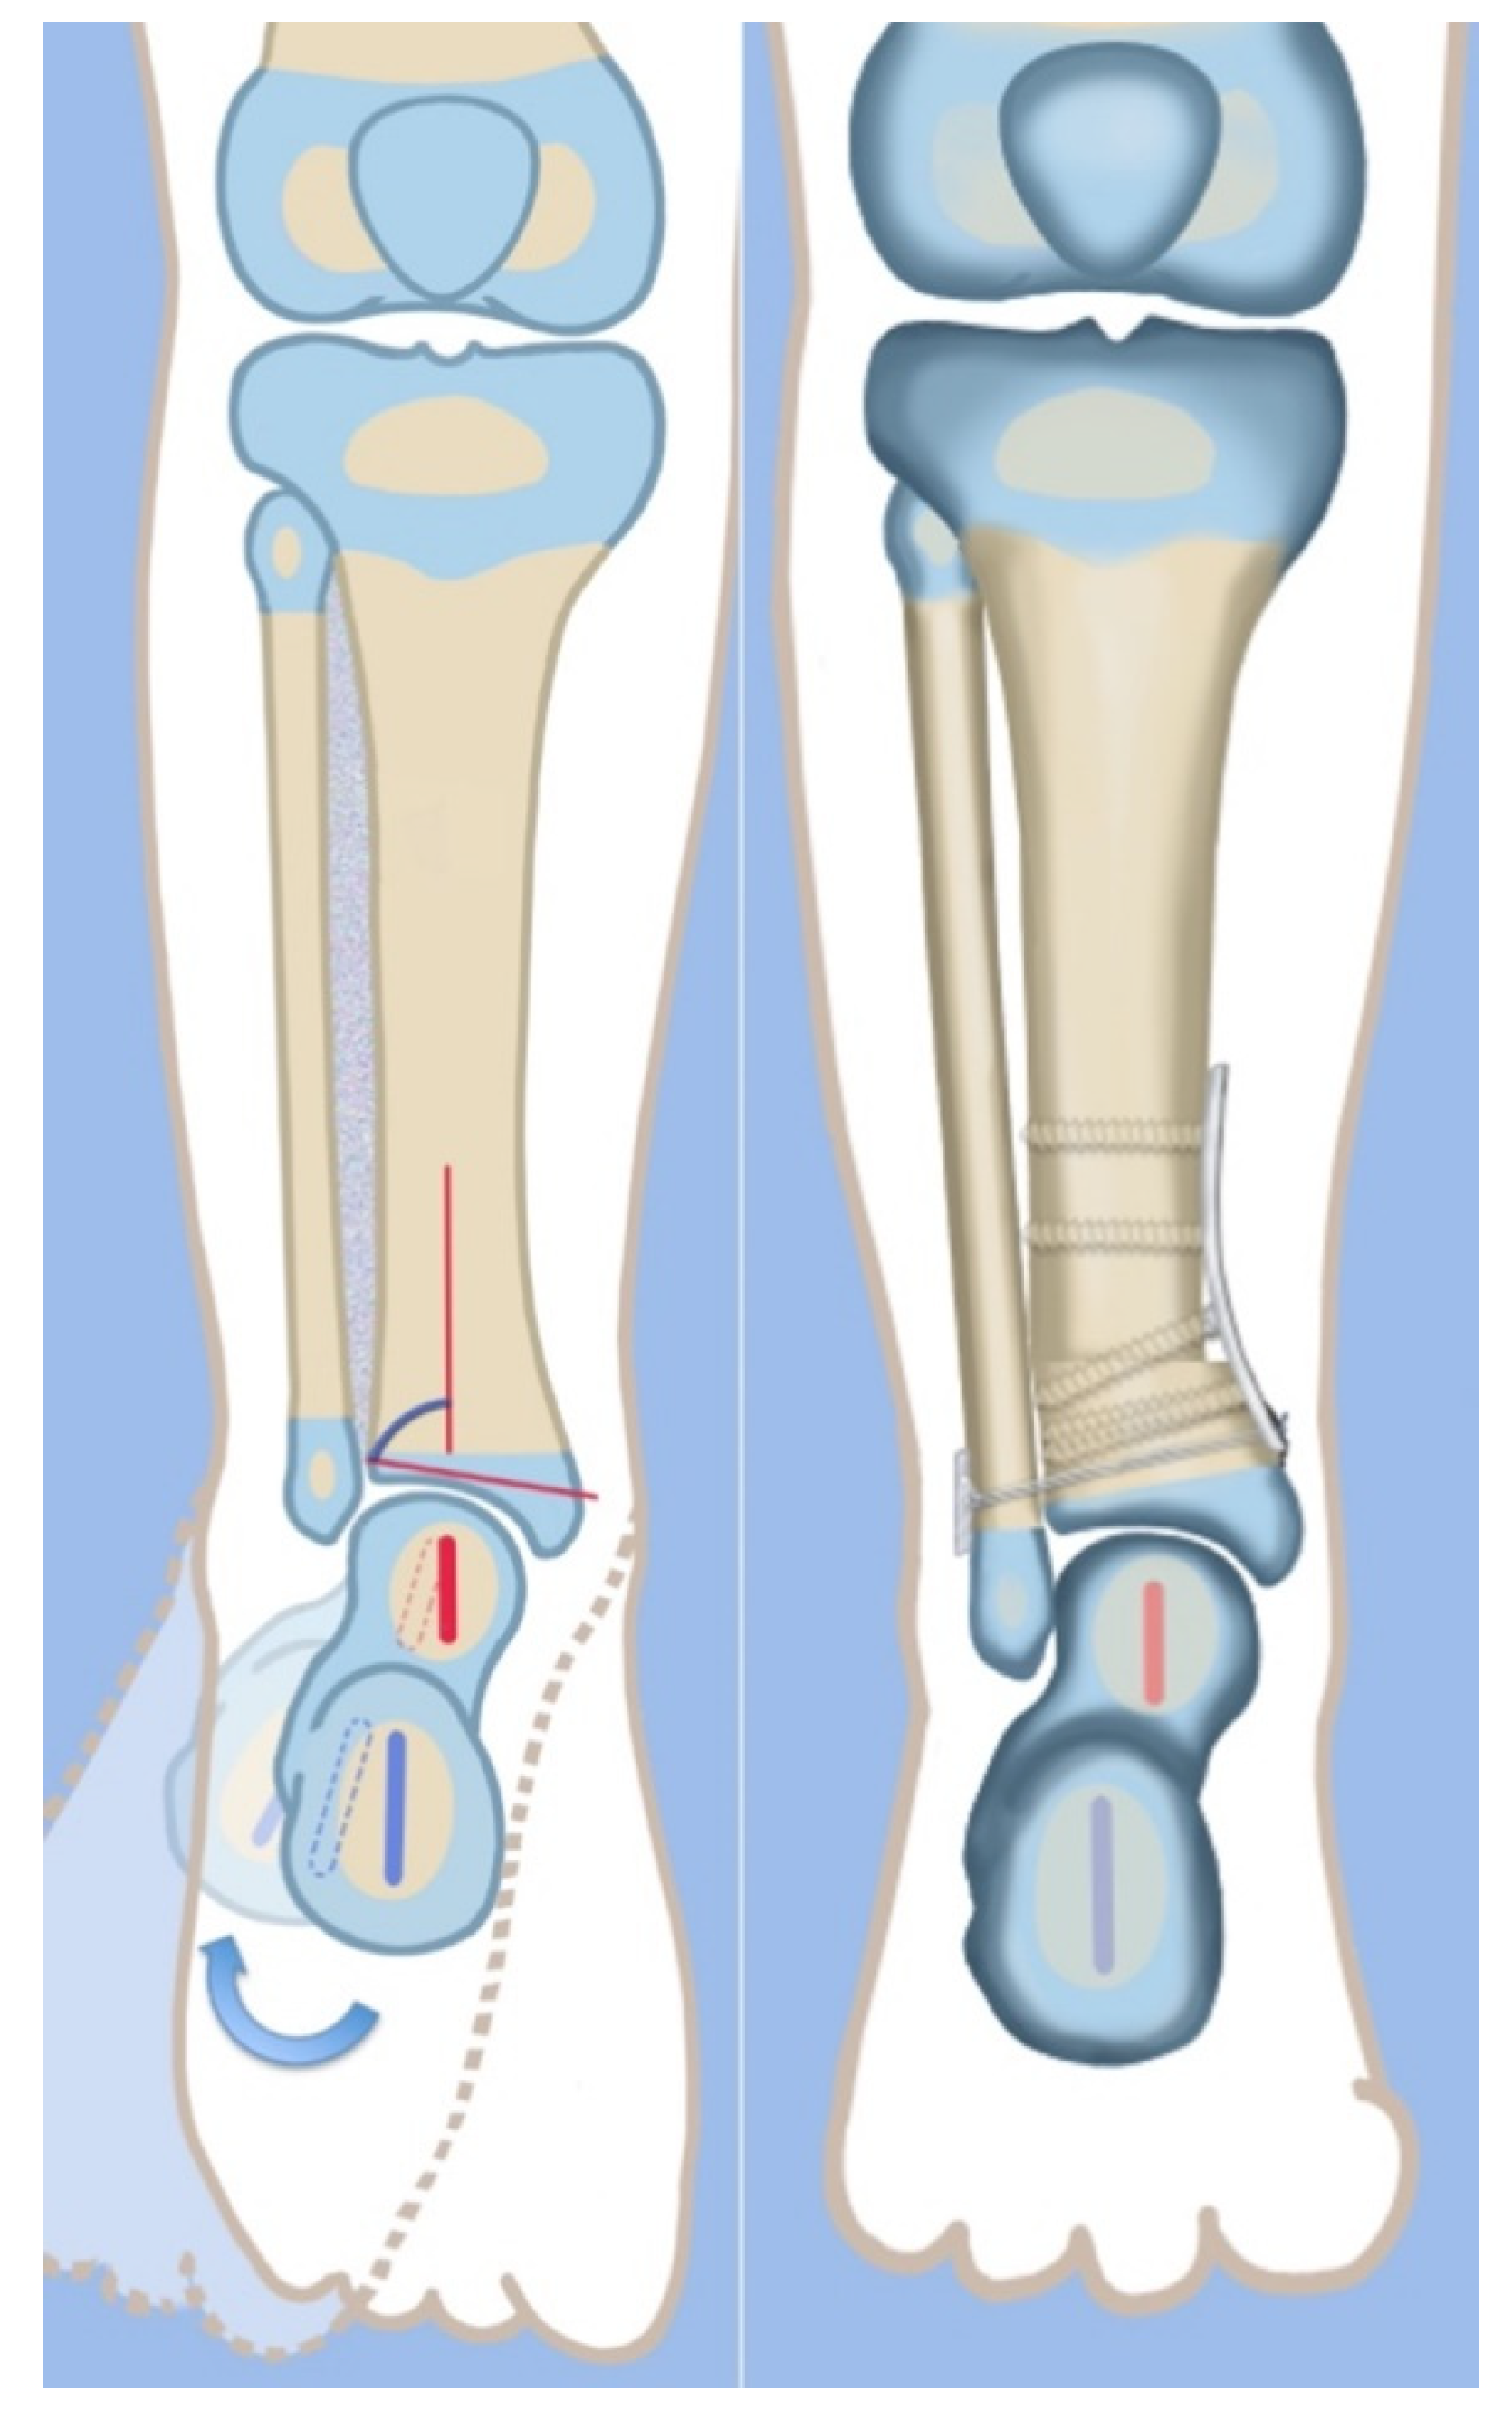

The SHORDT procedure (SHortening Osteotomy Realignment Distal Tibia) was designed by the senior author (D.P.) in 2014 to treat valgus instability of the ankle in patients who have a hypoplastic fibula with a distal fibula physis present [18] (Figure 4). This is commonly found in Paley type 2 FH. The SHORDT procedure involves a shortening and realignment tibial supramalleolar osteotomy to correct ankle valgus and procurvatum malorientation and lengthen the fibula relative to the tibia. This often results in a trapezoidal segment of bone being removed from the tibia and requires taking down the ankle syndesmosis before shortening the distal tibia. By shortening the tibia relative to the fibula, the fibula is effectively lengthened, restoring the buttressing effect of the lateral malleolus against dynamic ankle valgus. This addresses the foot and ankle deformity and instability in Paley type 2 FH and prepares the patient for concomitate or future leg lengthening. The SHORDT procedure does produce an acquired leg length discrepancy by the amount shortened that must be accounted for in future limb equalization.

Figure 4.

Illustrations before (left) and after (right) the SHORDT procedure (SHortening Osteotomy Realignment Distal Tibia) for dynamic valgus deformity of Paley type 2 FH. The main elements are the shortening and varusization of the tibial plafond relative to the fibula which does not change length. This eliminates the valgus instability of the ankle joint.